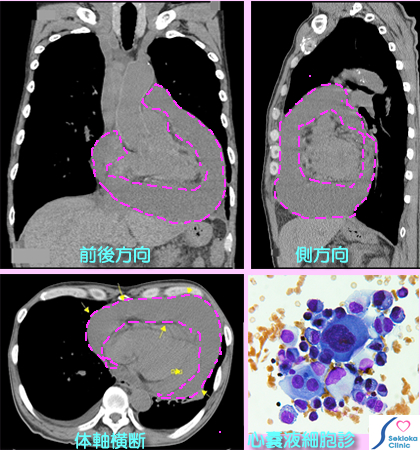

| 診断 | 身体検査では心嚢貯留液が多い場合、経静脈の怒張が見られます。聴診による心音異常から疑われることもあります。胸部X線撮影では心陰影の拡大から心嚢液貯留が疑われますが確定は困難。CT、超音波エコ-では確定診断が可能です。超音波エコー検査はその程度や心臓の動態まで詳細にわかります。下段の参考画像は 息切れ、食欲不振、体重減少で受診され、胸部MDCT検査で多量の心嚢液貯留が認められた例です。左側の挿入画像はMDCTの画像でピンク色の破線内が心嚢貯留液の範囲です。凡そ600mL以上あると推定されます。右側の動画はその超音波心臟エコー検査で、多量の心嚢貯留液の中に心臟は浮遊し、振り子様運動を呈しています。心臟は貯留液に圧排され、本来の拡張・血液の心腔内への充満が制限されるため、心拍出量が低下し、息切れ、減少した1回拍出量を補うため心拍数を増やして頻脈(自覚的には動悸)となります。この状態を心タンポナーデと呼びます。心嚢液貯留の原因が不明または多量貯留で危険な時は穿刺して排液します。本例は穿刺排液したところ液は血清で 液に含まれる細胞の顕微鏡検査(細胞診)でがんの転移と判明。左挿入画像の下段にその顕微鏡写真を示します。 |